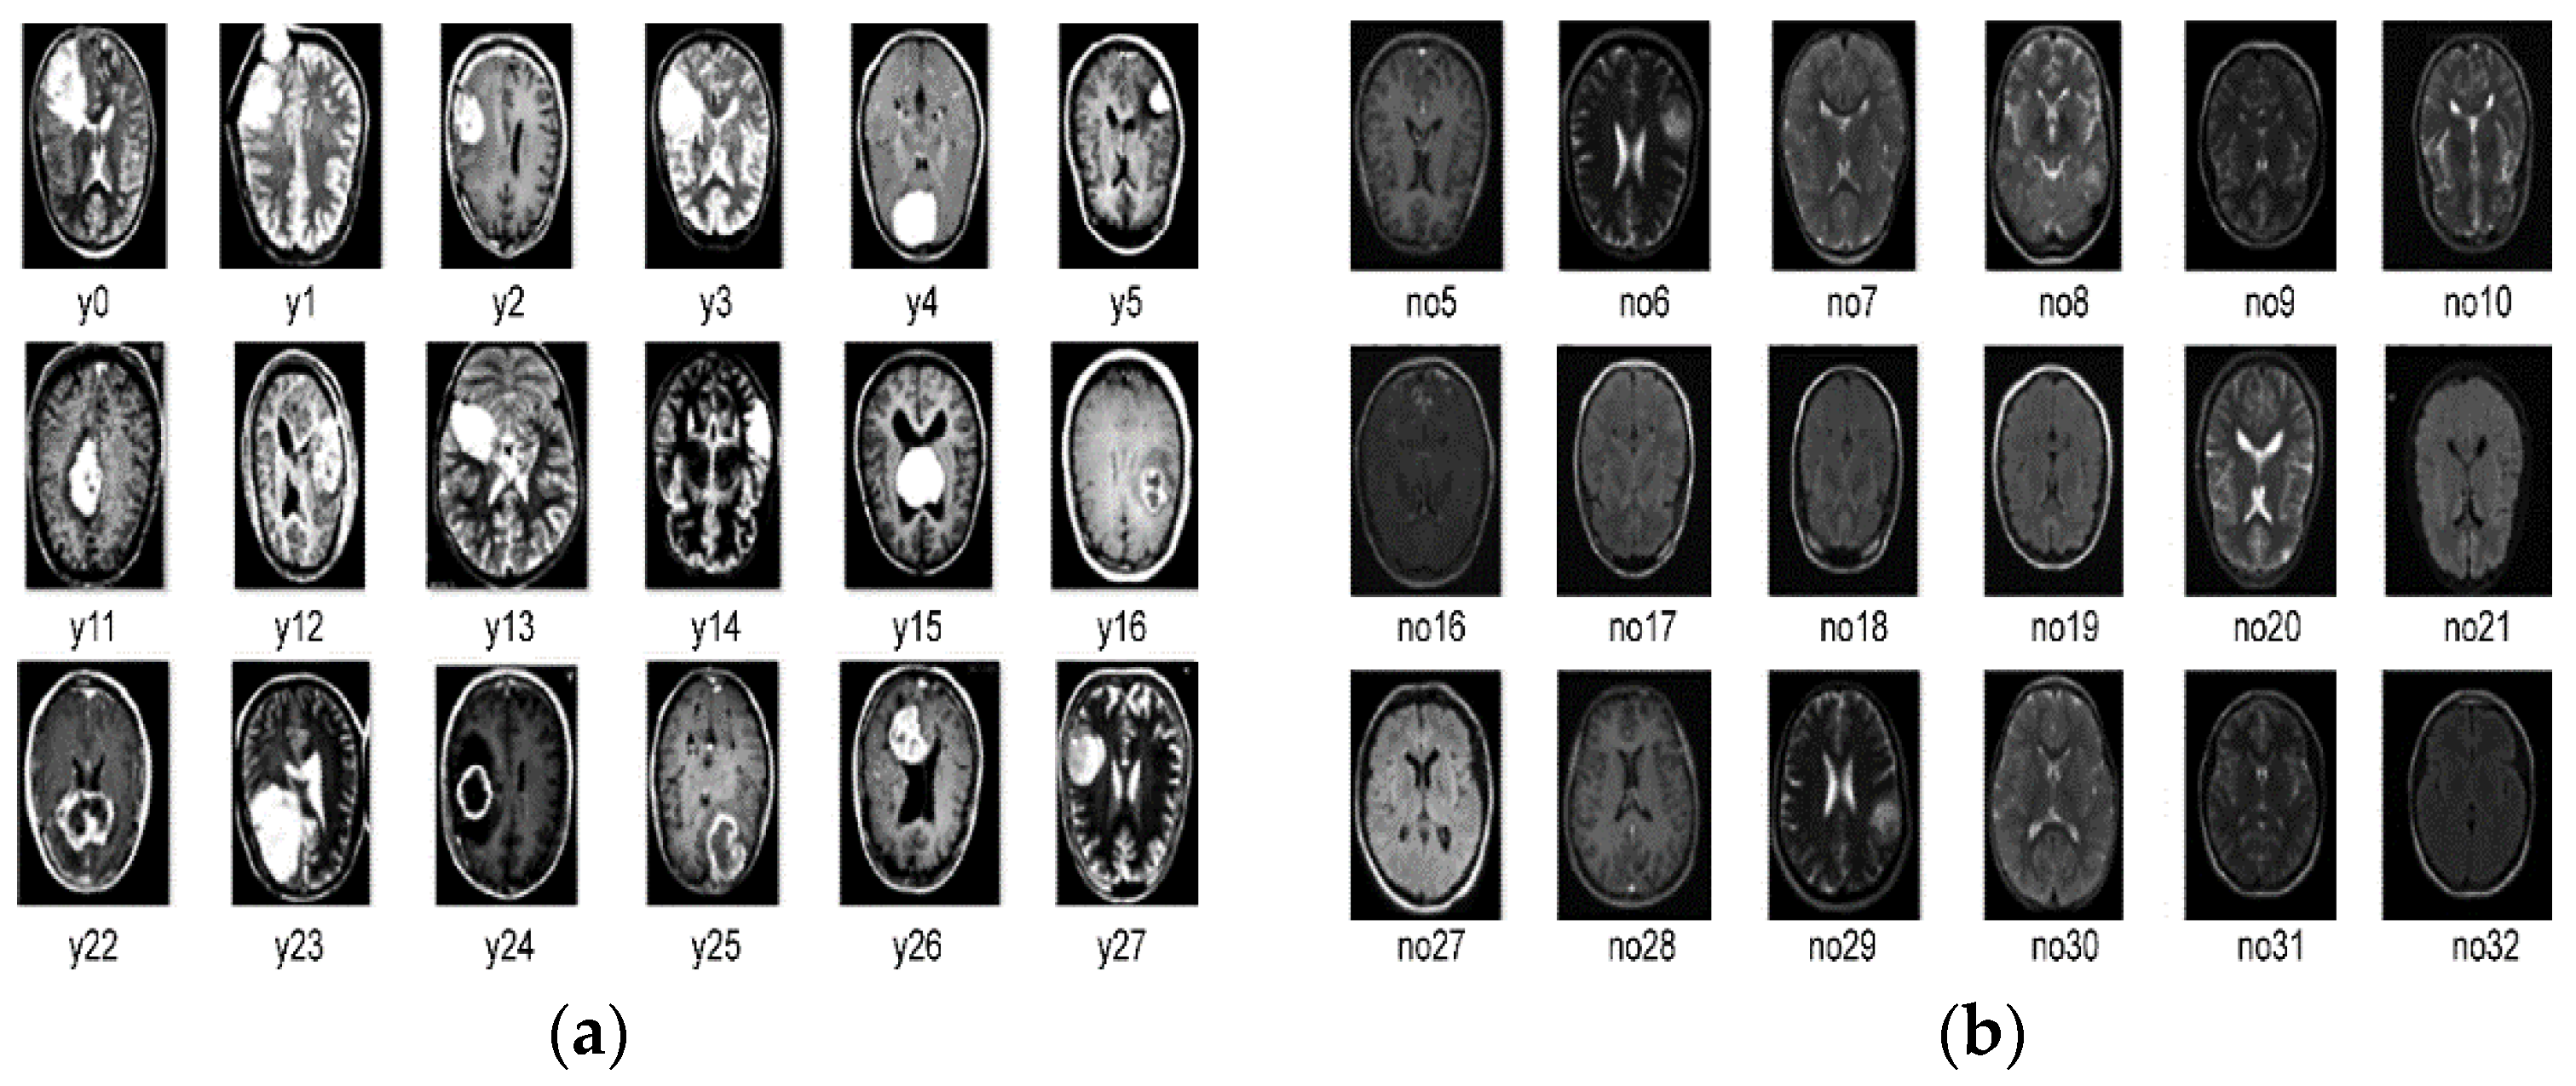

3.1. Brain Tumor Kaggle Dataset

3.2. Preprocessing of the Dataset